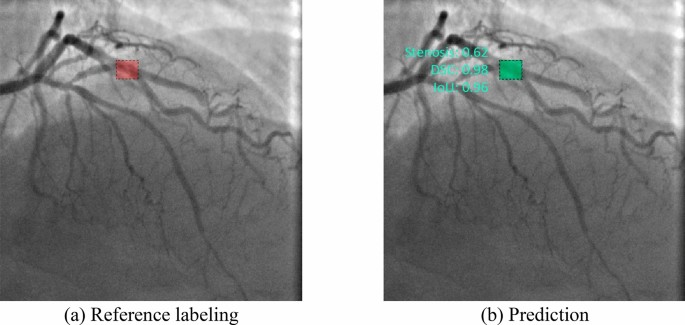

The capabilities of the selected neural networks are presented using the data of three patients with the referenced labeling (Fig. 9a–c). Detailed visualization for predictions is presented in Online Appendices H–J. The models with the best values of the loss function and mAP were used for testing.

Almost all models may accurately detect the location of stenosis. However, we faced several false positives while testing the Faster-RCNN NASNet model. In all three cases, this model detected the location of false stenotic segments with a probability of more than 90% in the right coronary artery (Fig. 9d) and the anterior descending artery (Fig. 9e, f) besides the reference stenotic region. SSD MobileNet V1 and SSD ResNet-50 V1 models failed to detect the location of stenosis in patient 1. SSD MobileNet V2 model demonstrated one of the best results in predicting the location of stenosis (Fig. 10). Despite the DSC metric of 0.65 in patient 3, it had the highest DSC metric in patients 1 and 2 (0.93 and 0.98, respectively). Additionally, the detectors based on the ResNet architecture, Faster-RCNN ResNet-50 V1 and Faster-RCNN ResNet-101 V2, should be noted. The average DSC metric on the test data was 0.85 and 0.84, respectively.